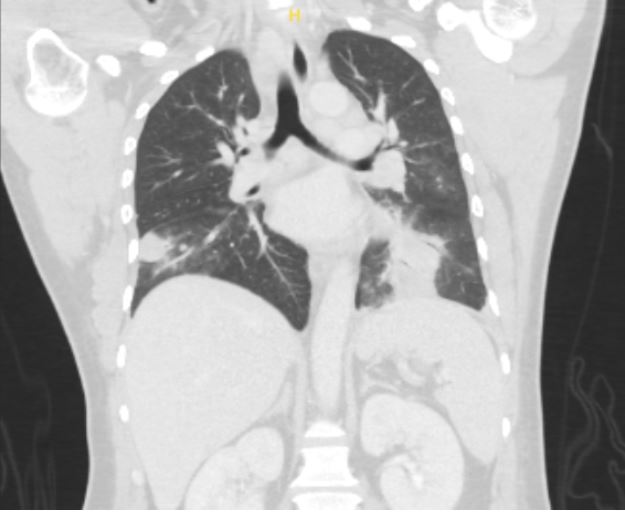

Case Presentation: A 36-year-old male with no significant medical history presented with one week of nocturnal fevers, rigors, cough associated with night sweats and 5 kg weight loss over one month. He immigrated from Guatemala 18 months ago, briefly lived in Arizona and Texas, and has worked as a landscaper locally for the past year. Review of system was negative for chest pain, shortness of breath, rashes, recent illness, or sick contacts. On admission, he had a fever of 39.4°C and was saturating 97% on room air. Physical exam was pertinent for course lung-sounds bilaterally and no skin rashes or ulcerations. Blood work was significant for leukocytosis (13.24 K/uL with neutrophilic predominance). CT Chest showed mass-like opacities in the bilateral lower lobes and left upper lobe, mediastinal and hilar lymphadenopathy, bilateral pleural effusions, and a 6mm right lung nodule (figure 1 and 2), raising concerns for neoplastic, rheumatologic, and/or infectious etiology. Our initial infectious workup, including blood and sputum cultures, HIV testing, tick-borne panel, and endemic mycoses was negative and the patient showed no improvement of symptoms or leukocytosis despite treatment with cefepime and azithromycin. On hospital day 7, bronchoscopy with lymph node biopsy was performed. Fevers persisted despite treatment with cefepime, azithromycin, and minocycline. Further infectious workup for fungal pathogens, Tuberculosis, and Coxiella was negative. Rheumatologic and oncologic workup with ANA, RF, vasculitis panel, and peripheral flow were also negative. On hospital day 14, send out testing for Tularemia IgG and IgM was positive, alongside pathology showing necrotizing granulomas positive for Francisella tularensis DNA. His antibiotic regimen was switched to IV gentamicin and PO doxycycline, leading to immediate symptom improvement on day 2 of treatment. The patient completed 10 days of targeted antibiotic therapy in-patient due to lack of insurance, with rapid resolution of fever, leukocytosis, and symptoms.